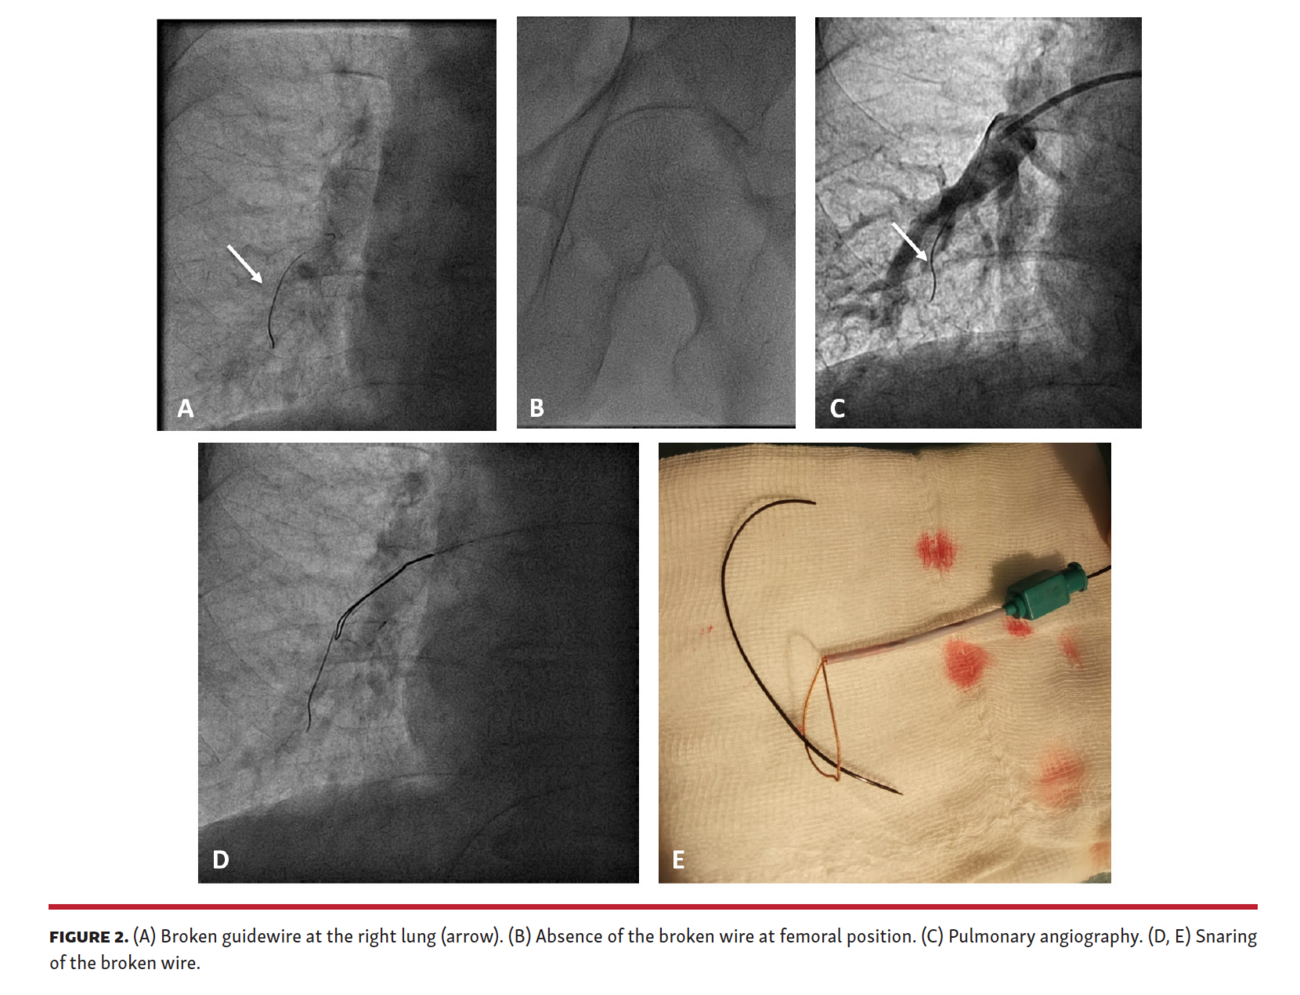

Ten days later, the patient underwent a new coronary angiography for chest pain. A radiopaque linear element at the right lung was observed (Figure 2A). The broken wire was not in the previous femoral position (Figure 2B), and we deduced that it was initially in the femoral vein and migrated to the pulmonary artery. After discarding any coronary complication, we advanced a guiding catheter to the right pulmonary artery, performed an angiography (Figure 2C; Video 3), and snared the broken wire, resulting in successful retrieval (Figure 2D-2E; Video 4). Guidewire-related complications are rarely reported, but are associated with significant mortality and morbidity. Although the radial approach is preferred in the majority of cases, the femoral approach is needed in some complex procedures. Ultrasound guidance decreases complications. Additionally, the use of plastic wires with metallic needles can produce wire rupture.